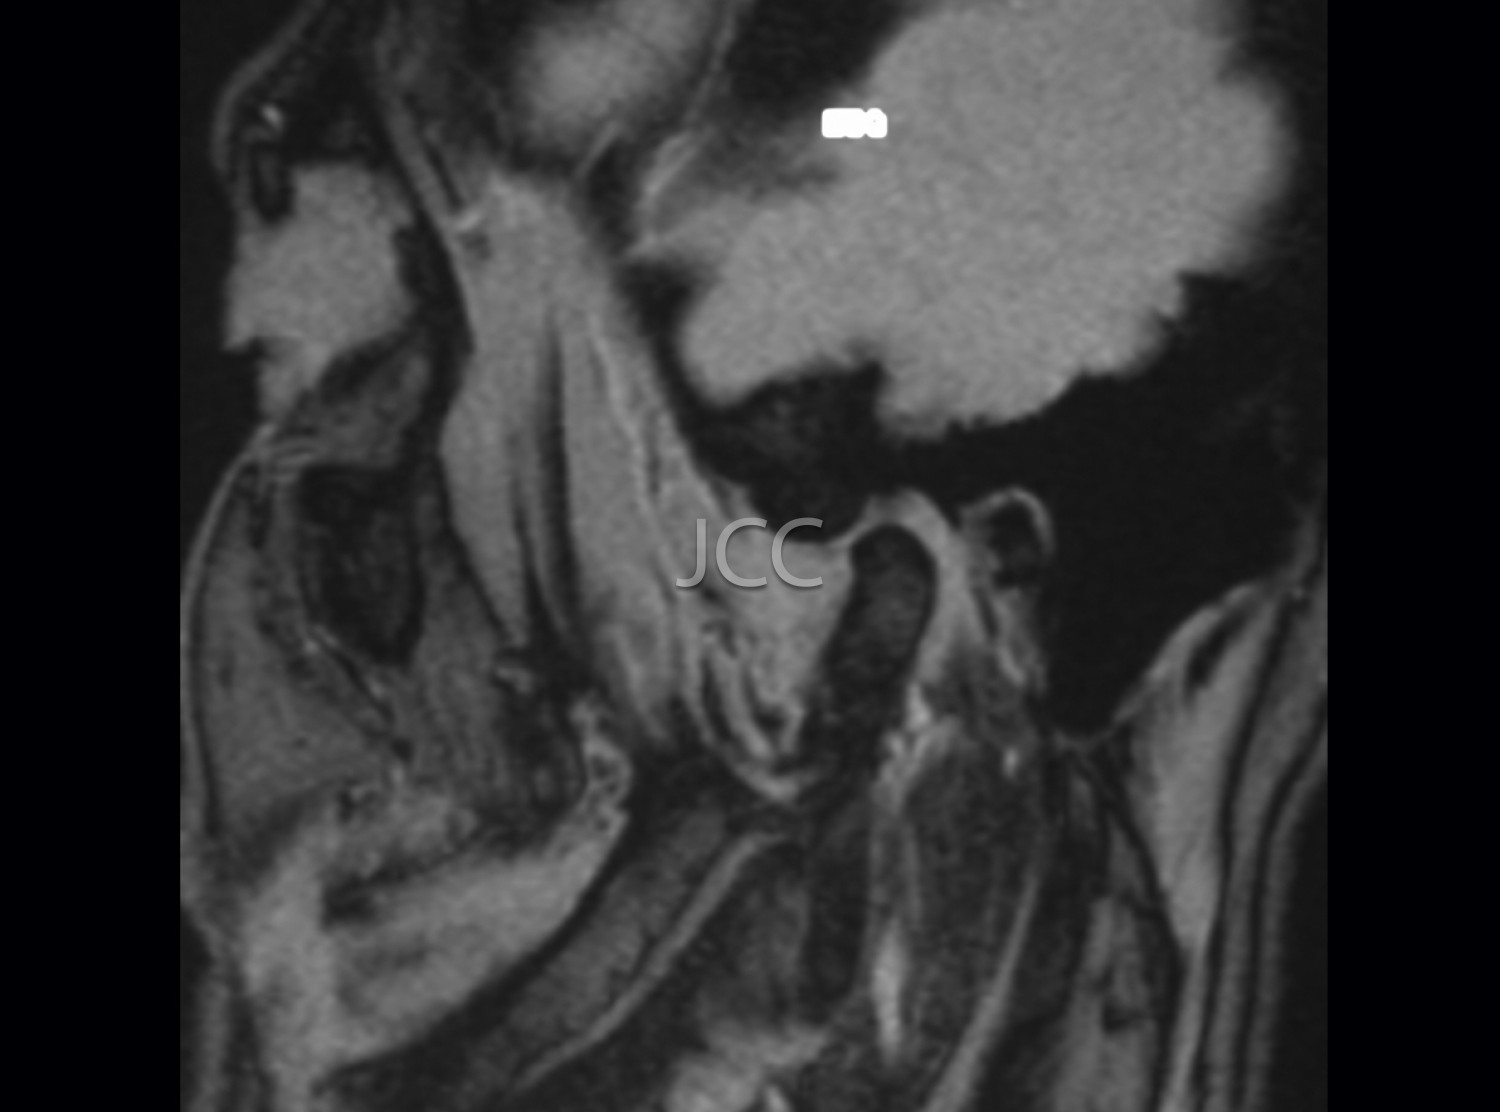

MRI is currently the first-line examination for the study of TMJs pathology. They allow the dynamic study of the relationship of the articular disc and mandibular condyle in the various degrees of buccal opening.